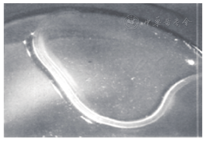

患者女,53岁。2015年6月25日因"右眼痒伴异物感1月"就诊。2个月前有飞虫入眼,1月后自觉右眼痒异物感不适。家养狗,且长期与其同床睡觉。2周前曾自己从右眼结膜囊内取出1条白色线状小虫。当地医院曾按"结膜炎"治疗,眼痒未见好转来我院就诊。门诊检查:双眼视力1.0;双眼眼睑、球结膜未见明显充血,裂隙灯下翻转右眼上睑,结膜囊上穹窿部颞侧可见白色透明线状虫体,游走活跃,或呈团状或结状(图1)。双眼前节及玻璃体眼底未见异常。1%丙美卡因右眼表面麻醉后,在裂隙灯下用眼科镊取出2条白色线状活虫体(图2)。生理盐水冲洗结膜囊后,再次反复检查双眼,未发现虫体。在光学显微镜下观察:虫体长10~12 mm,在生理盐水中保存4 h后活动(+),乳白色,线虫头端圆盾,体表有皱褶横纹。经华中科技大学同济医学院寄生虫教研室鉴定:2条均为眼结膜吸吮线虫(雄性及雌性各1条)。诊断:右眼结膜吸吮线虫病。给予左氧氟沙星眼液局部治疗。随访1月未复发。